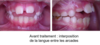

Lorsque la langue n'est pas à sa place au plais et s'interpose entre les arcades, on peut voir apparaître une béance antérieure.

La correction de la posture linguale  (c'est à dire la position de la langue au repos) et de la fonction linguale (c'est à dire lorsque la langue est en activité, notamment lors de la déglutition) sont indispensables pour atteindre l’ensemble des objectifs du traitement et pour faire en sorte que les résultats obtenus soient les plus stables possibles.

CAS CLINIQUE : fermeture d'une béance antérieure grâce au port d'une ELN